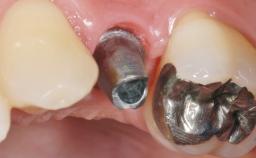

Peri-Implant Mucositis Treatment Outcomes on an Implant with a Submucosal Restoration Margin

Mauricio Araujo and Flauvia Matarazzo present this straightforward clinical case, demonstrating the potential effect of implant placement depth on the resolution of peri-implant treatment. A 42-year-old systemically healthy female patient, a non-smoker with no history of periodontitis, was treated at the Dental Clinic at the State University of Maringá, Brazil between 2008 and 2009, when she received five implants restored with single crowns at sites 14, 26, 27, 36, and 46. After delivery of the implant-supported prosthetic restorations, the patient was enrolled in the supportive peri-implant therapy (SPiT) maintenance program at the same university.